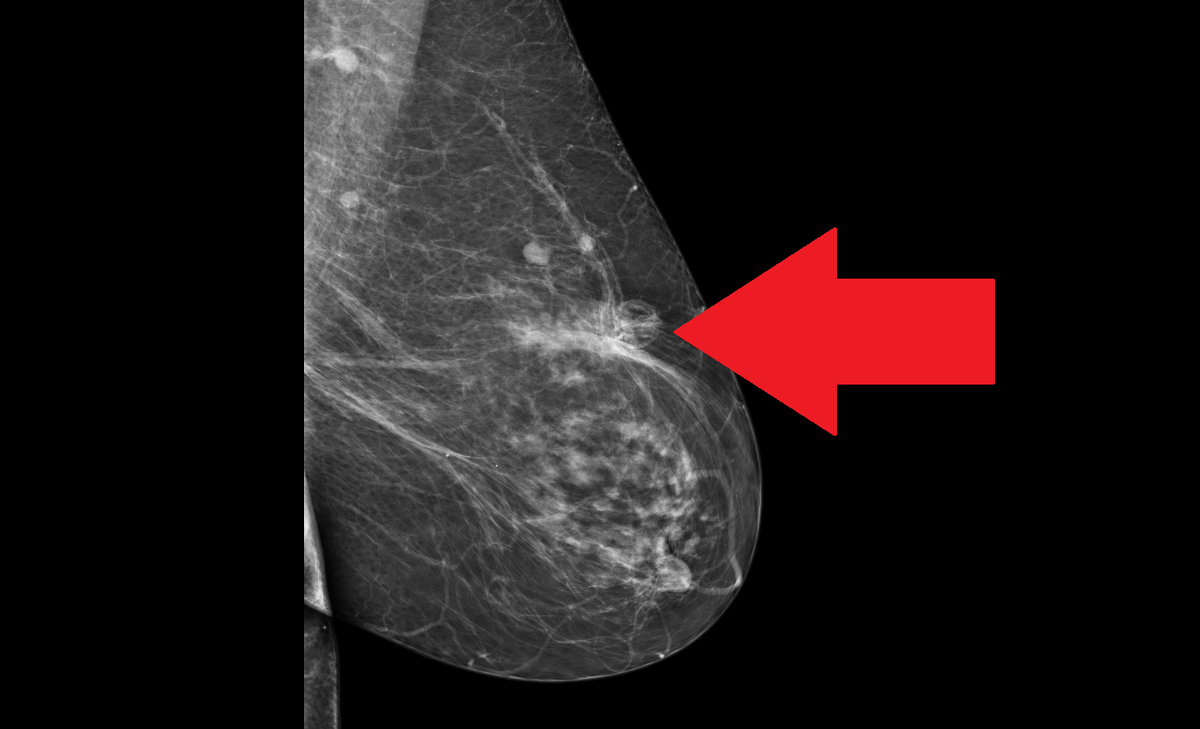

Примерно за три месяца до текущего обращения ко мне я оперировал пациентку по поводу рака молочной железы. Всё было в порядке, швы сняты, пациентка отправлена под динамическое наблюдение с контрольным обследованием через три месяца. Каково же было мое удивление, когда через три месяца после операции по данным маммографии в ткани молочной железы в зоне послеоперационного рубца была выявлено новообразование неправильной формы, с нечетким контуром, да еще и размерами 40х21мм - BI-RADS-5. BI-RADS5 – это значит, что у врача рентгенолога, описывающего маммографию, даже сомнений не было в злокачественной природе новообразования. Такое заключение нельзя игнорировать. С другой стороны, после операции прошло всего-то три месяца, рецидив не должен был возникнуть в столь короткое время. Пальпаторно под послеоперационным рубцом определялось овальной формы безболезненное несмещаемое уплотнение. Первым делом я оценил характеристики новообразования по УЗИ – и успокоился почти полностью. По УЗИ опреде